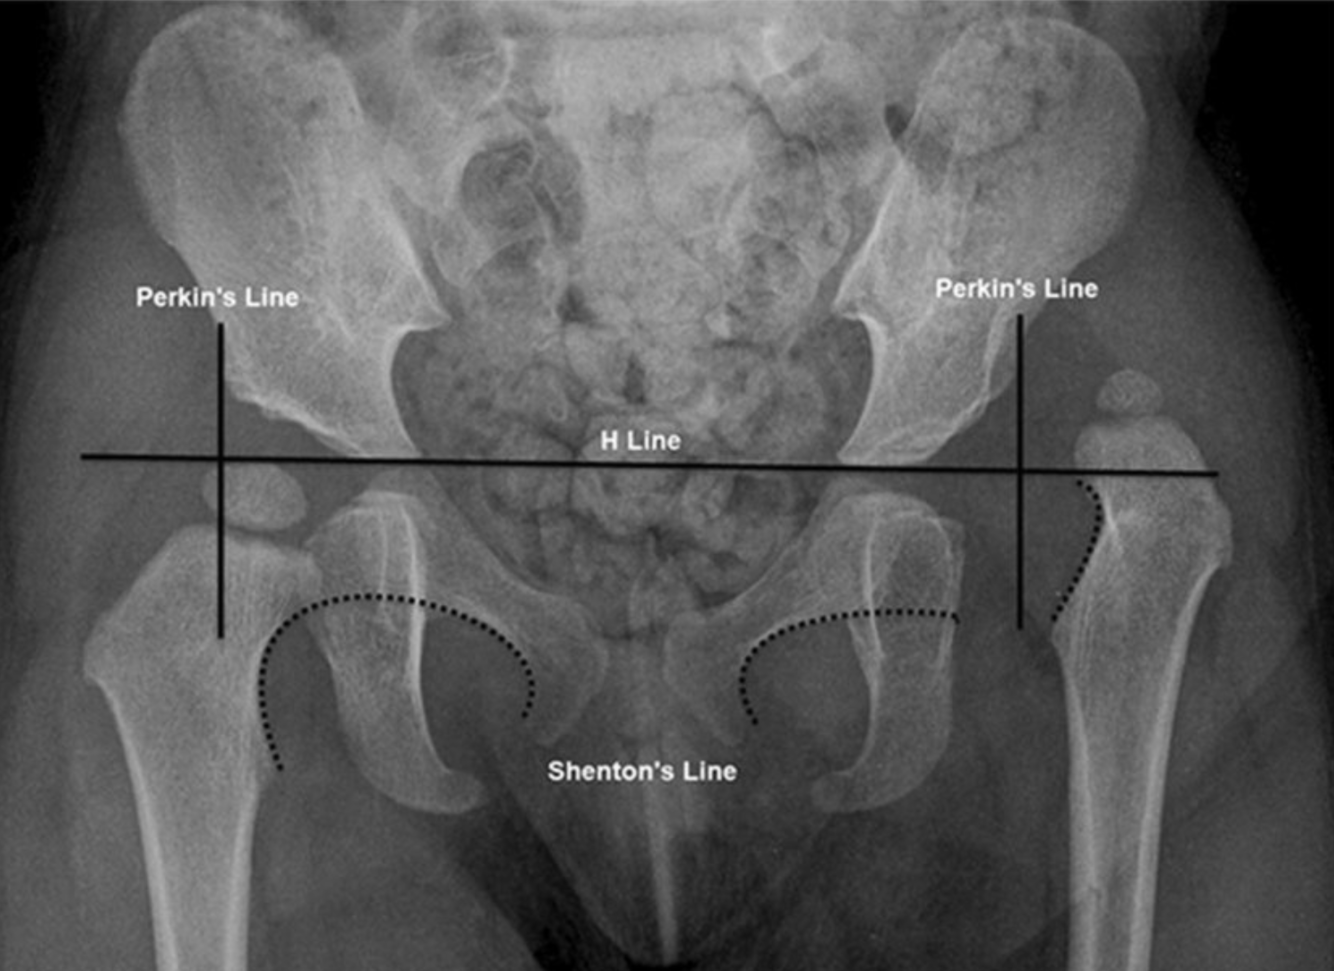

What is the Hilgenreiner line?

The Perkins line and Shenton arc on radiography. Anteroposterior radiograph in a 2-year-old girl with left developmental dysplasia of the hip. The Perkins line is drawn perpendicular to the Hilgenreiner line (H line) and intersects the lateral acetabular rim. The Shenton arc is formed by the medial cortex of the femoral neck and the inferior cortex of the superior pubic ramus (dotted lines). The normal right hip shows the femoral head confined to the inferomedial quadrant and a continuous Shenton arc. The abnormal left hip shows the dislocated femoral head within the superolateral quadrant and a discontinuous Shenton arc

https://www.researchgate.net/figure/The-Perkins-line-and-Shenton-arc-on-radiography-Anteroposterior-radiograph-in-a_fig10_337009090